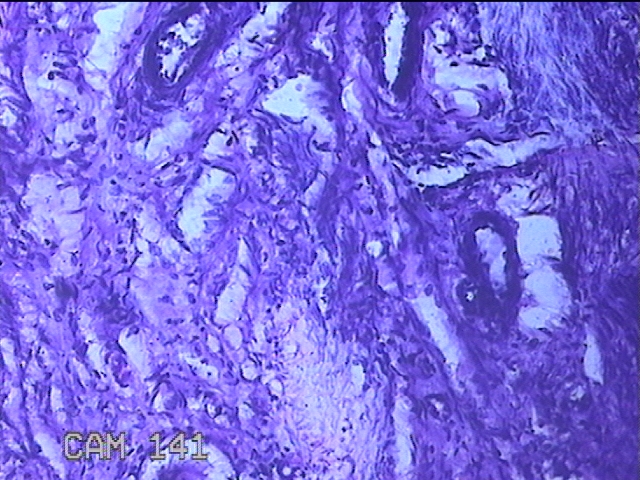

子宫憩室

性别

女

年龄

39岁

临床诊断

1.异常子宫出血 2.子宫切开憩室 3.地中海贫血 4.胃溃疡

一般病史

经期延长7年。

标本名称

大体所见

灰白粉红色不规则组织3x2.8x0.8cm一块。